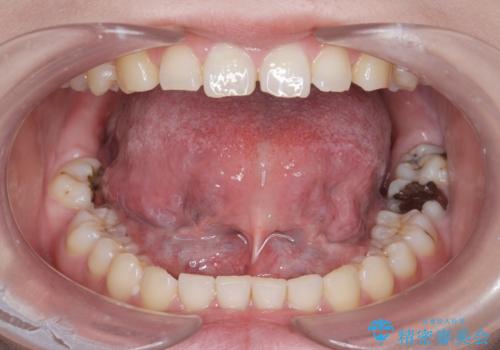

[舌小帯の形成術] 舌の動きが悪い 滑舌を改善したい!

滑舌の改善 舌小帯の形成術